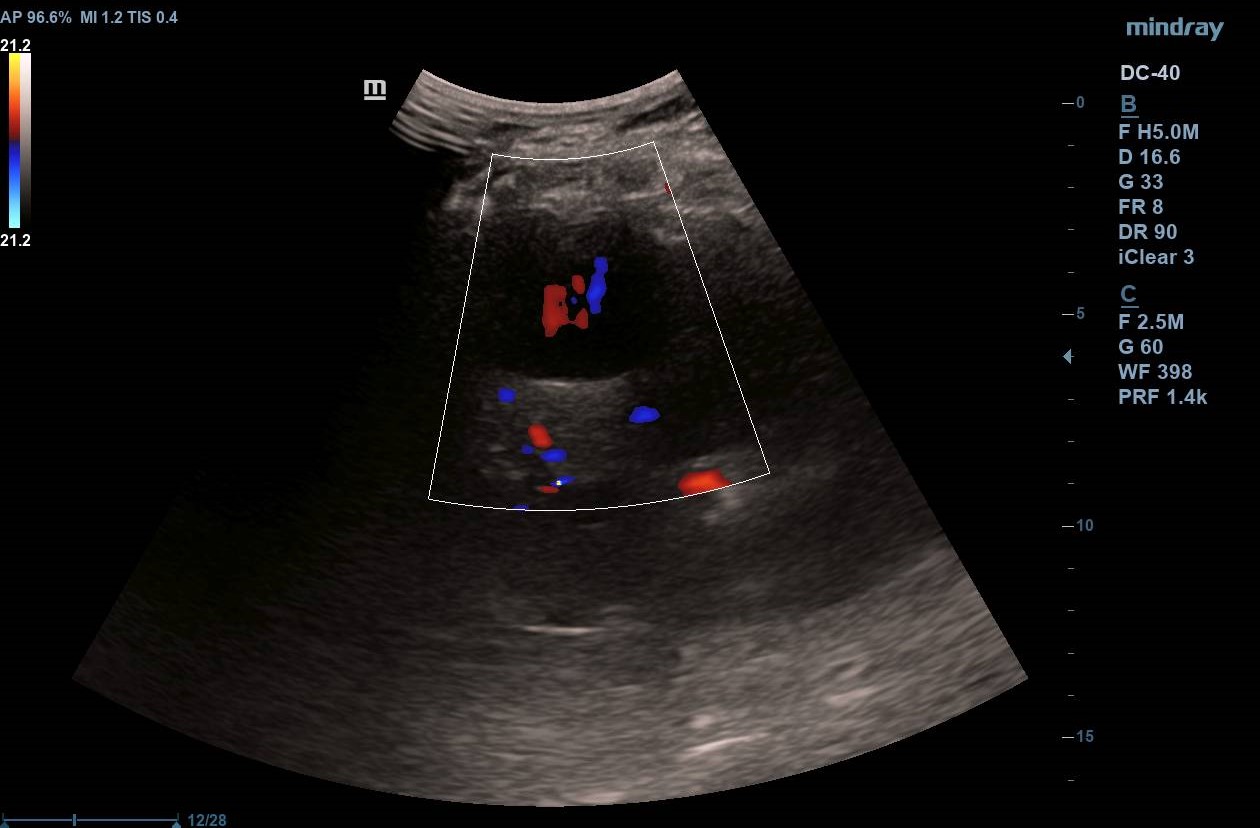

Ecografía inicial con ecógrafo portátil con múltiples LOES hepáticas hipoecogénicas de 5-6 cm de diámetro, alguna con centro hiperecogénico (figuras 1 y 2), que se confirman con ecógrafo de consola (figuras 3 y 4) con flujo Doppler aumentado respecto al resto de parénquima (hay vídeos).